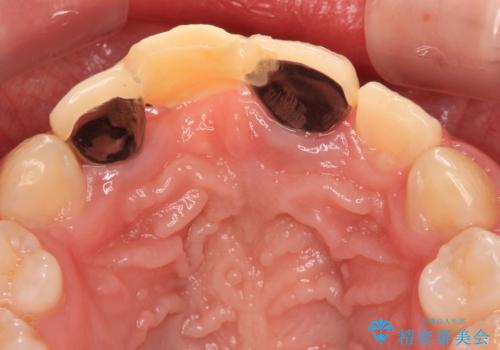

小学生の頃に歯をぶつけて抜歯となりブリッジを装着したそうですが、その後矯正治療を行うに当たりブリッジを切断したとのことでした。

残っている歯根の状態はあまり良くなく、長期的な予後を考えると抜歯を検討するべきでしたが、20代前半という年齢を考え、オールセラミックブリッジにて補綴治療を行うこととしました。